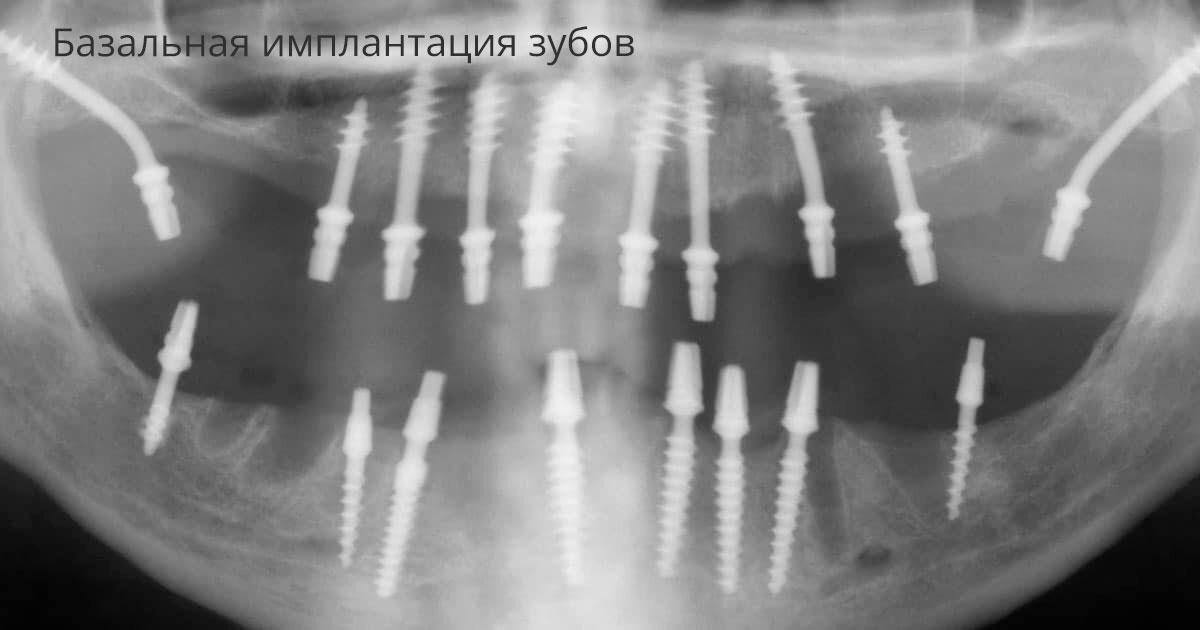

Базальная имплантация верхней челюсти

Базальные импланты устанавливаются не в верхний слой кости, который часто атрофируется, а в более глубокие и плотные участки. Благодаря этому они держатся очень надёжно, даже если кость у пациента тонкая. Это главное отличие от классических имплантов, которые требуют достаточного объёма кости.